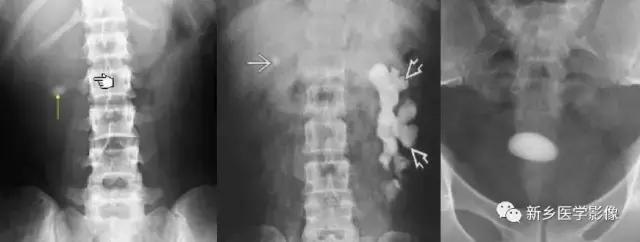

胆结石

可完全钙化,也可以表现为环形钙化,如胆囊切除术也可以导致结石脱落至肝下隐窝。

14

阑尾结石(粪石)

主要位于右下腹部,表现为结节状、扁条状钙化。